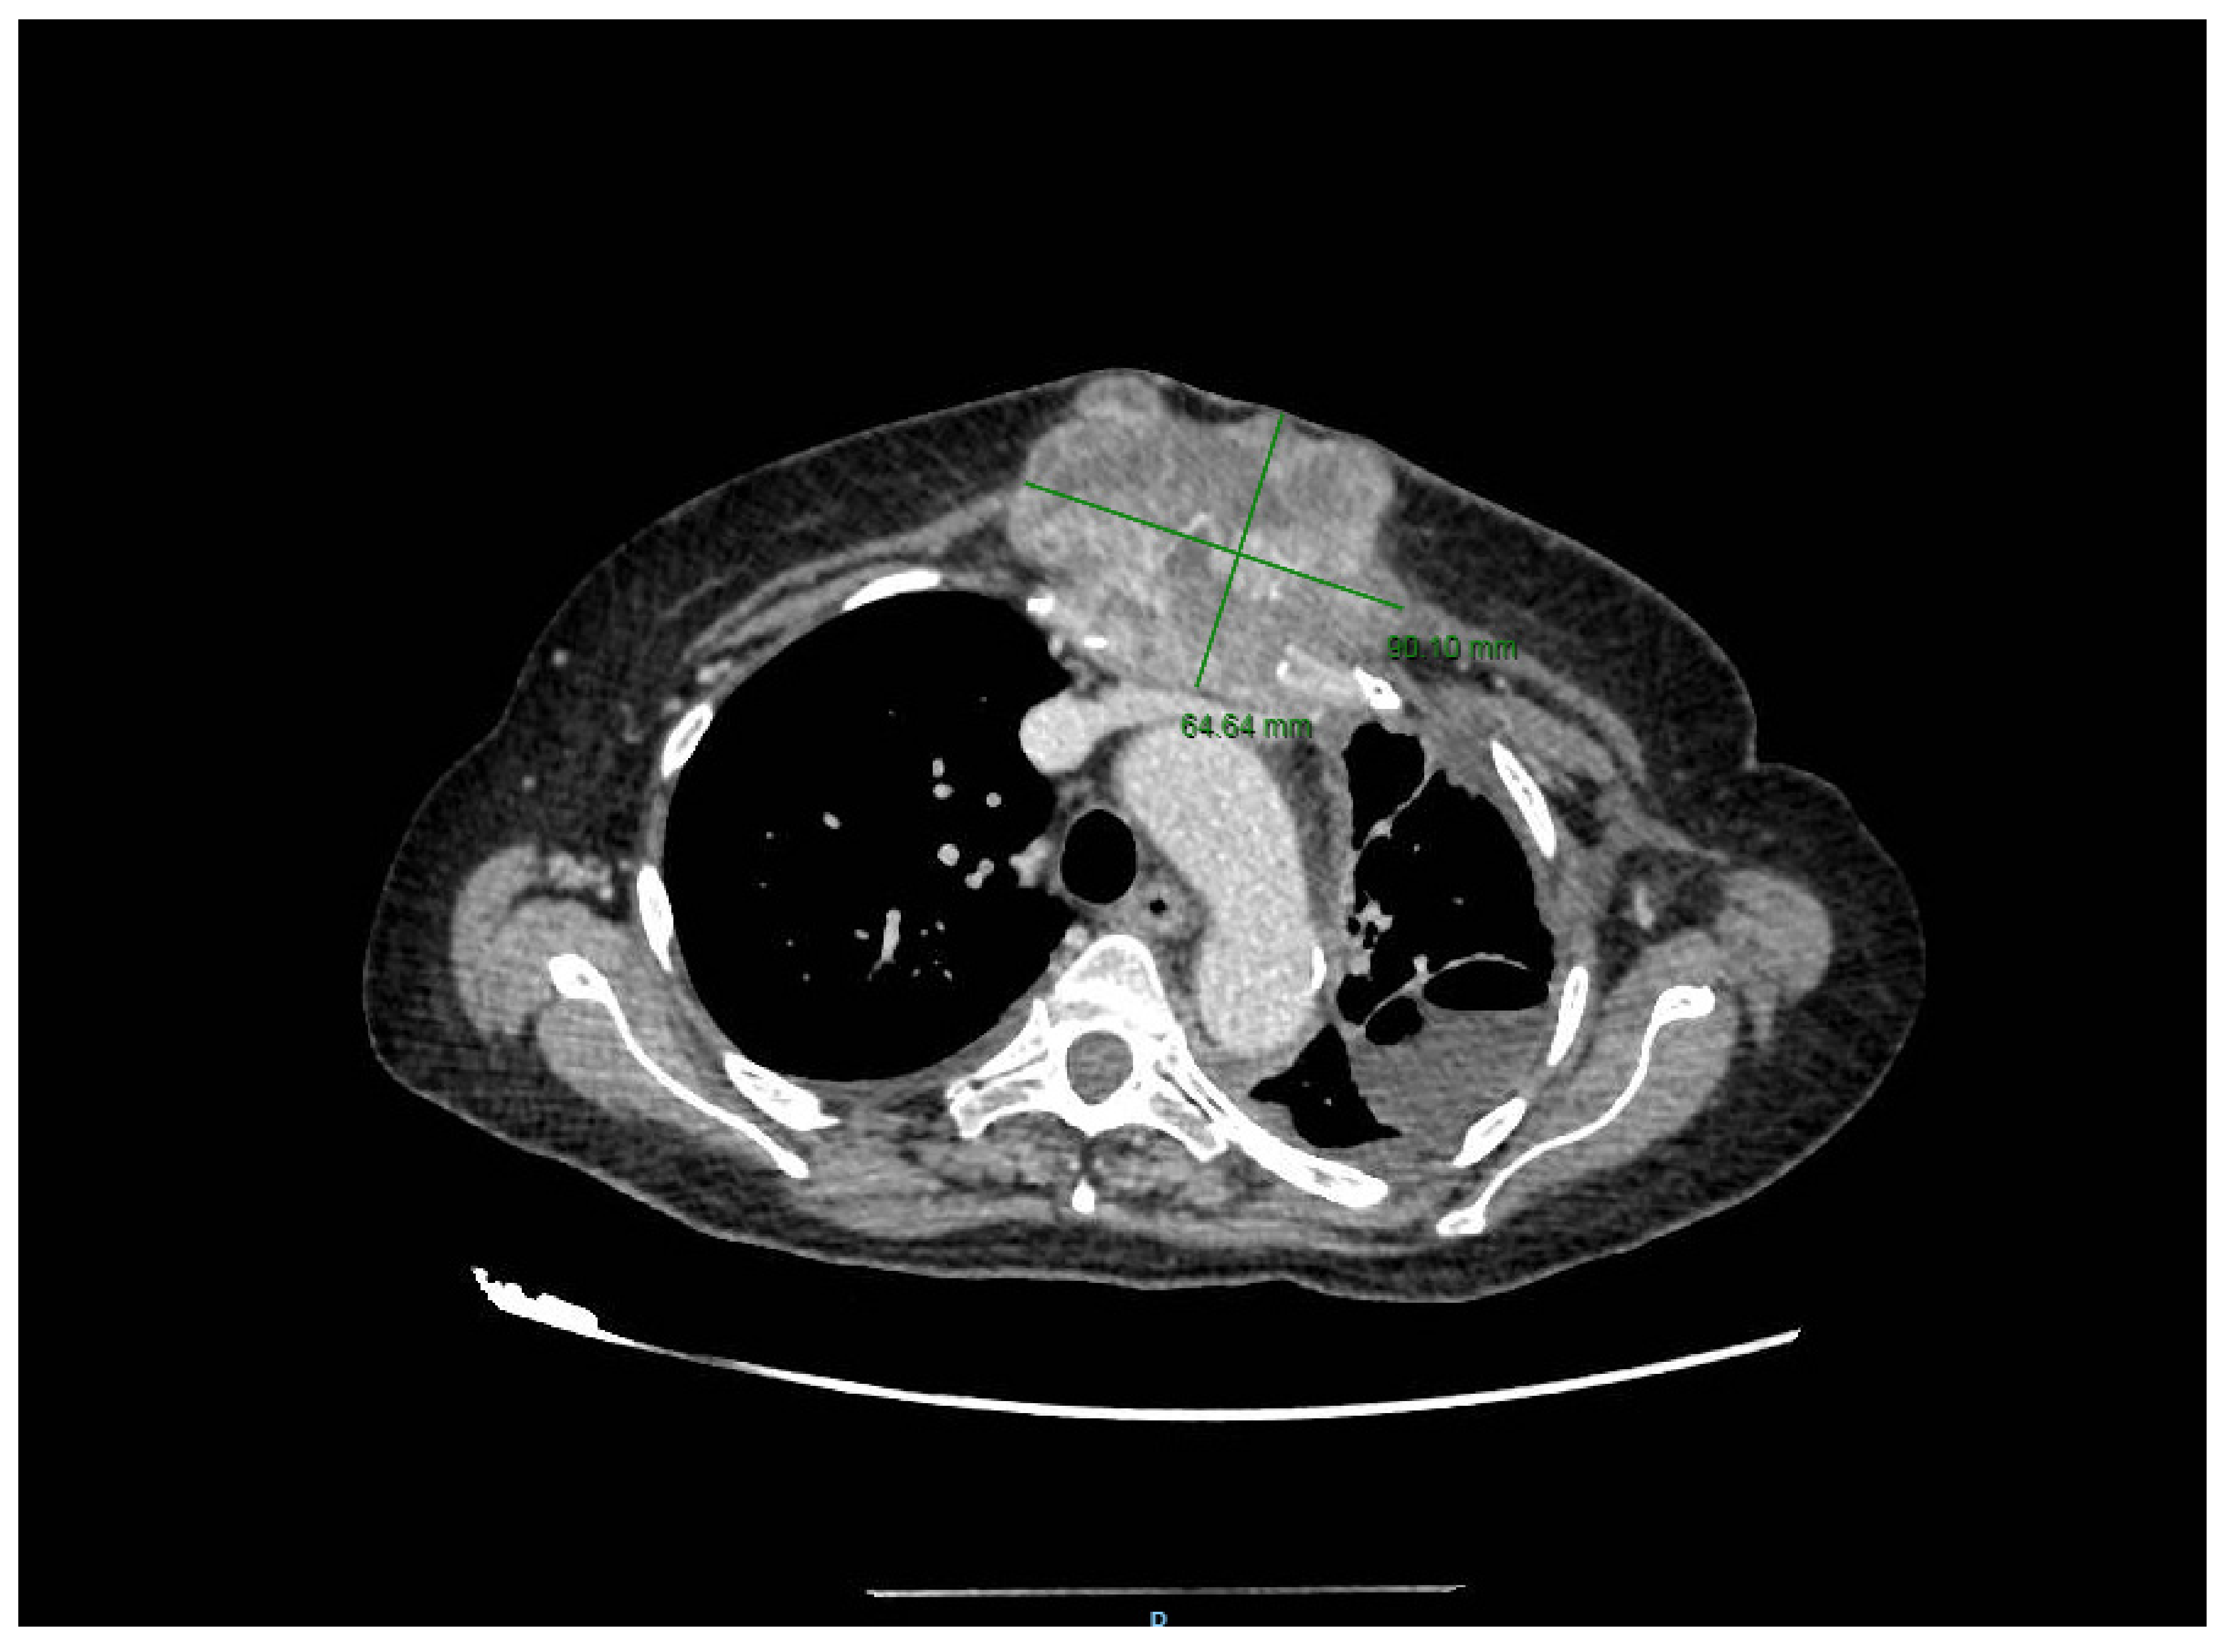

2. Case Presentation